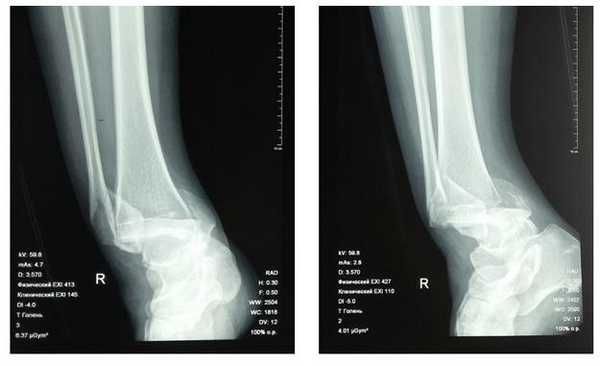

Клинический случай 2. Перелом обеих лодыжек с вывихом стопы кнаружи, кзади.

44 А3-3

Пациентка Л. 50 лет, травма в быту, получила закрытый перелом обеих лодыжек с вывихом стопы кнаружи и кзади. Данный случай интересен значительным повреждением мягких тканей произошедшем при травме и потребовавшем значительных усилий в борьбе с отёком, а также морфологией перелома внутренней лодыжки, сломавшейся одним большим блоком вместе с задним краев большеберцовой кости, что потребовало её фиксации при помощи пластины и винтов.

В связи с выраженным отёком мягких тканей, высоким риском некроза краёв ран и инфекционных осложнений пациентке с целью предоперационной подготовки выполнялись скелетное вытяжение, сосудистая и метаболическая терапия, лимфодренаж, физиотерапия. После спадения отёка, на 3 день после поступления выполнено оперативное вмешательство: открытая репозиция, остеосинтез переломов наружной и внутренней лодыжек пластинами и винтами.

Через 4 дня пациентка выписана на амбулаторное долечивание. Послеоперационные раны зажили первичным натяжением, швы удалены через 14 дней.

Через 6 недель после первичного вмешательства произведено удаление позиционного винта, пациентка приступила к активной разработке движений в голеностопном суставе.

Амплитуда движений через 8 недель после травмы и оперативного вмешательства по поводу этого тяжёлого повреждения близка к полной. Пациентка ходит с полной опорой, не используя костыли или трость, не хромает, боли не беспокоят. Сохраняется умеренный отёк в области голеностопного сустава.